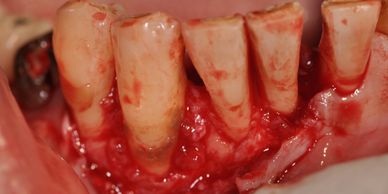

從日常洗牙維護,牙周統合照護到自費牙周手術,美日牙醫均提供服務,不同於其它診所,我們牙周手術以不添加外來骨粉而是建議癒後與再發率較低的傳統清創消除式牙周手術,另外,不想開刀處理,在評估後也可以選擇自費雷射顯微牙周治療。